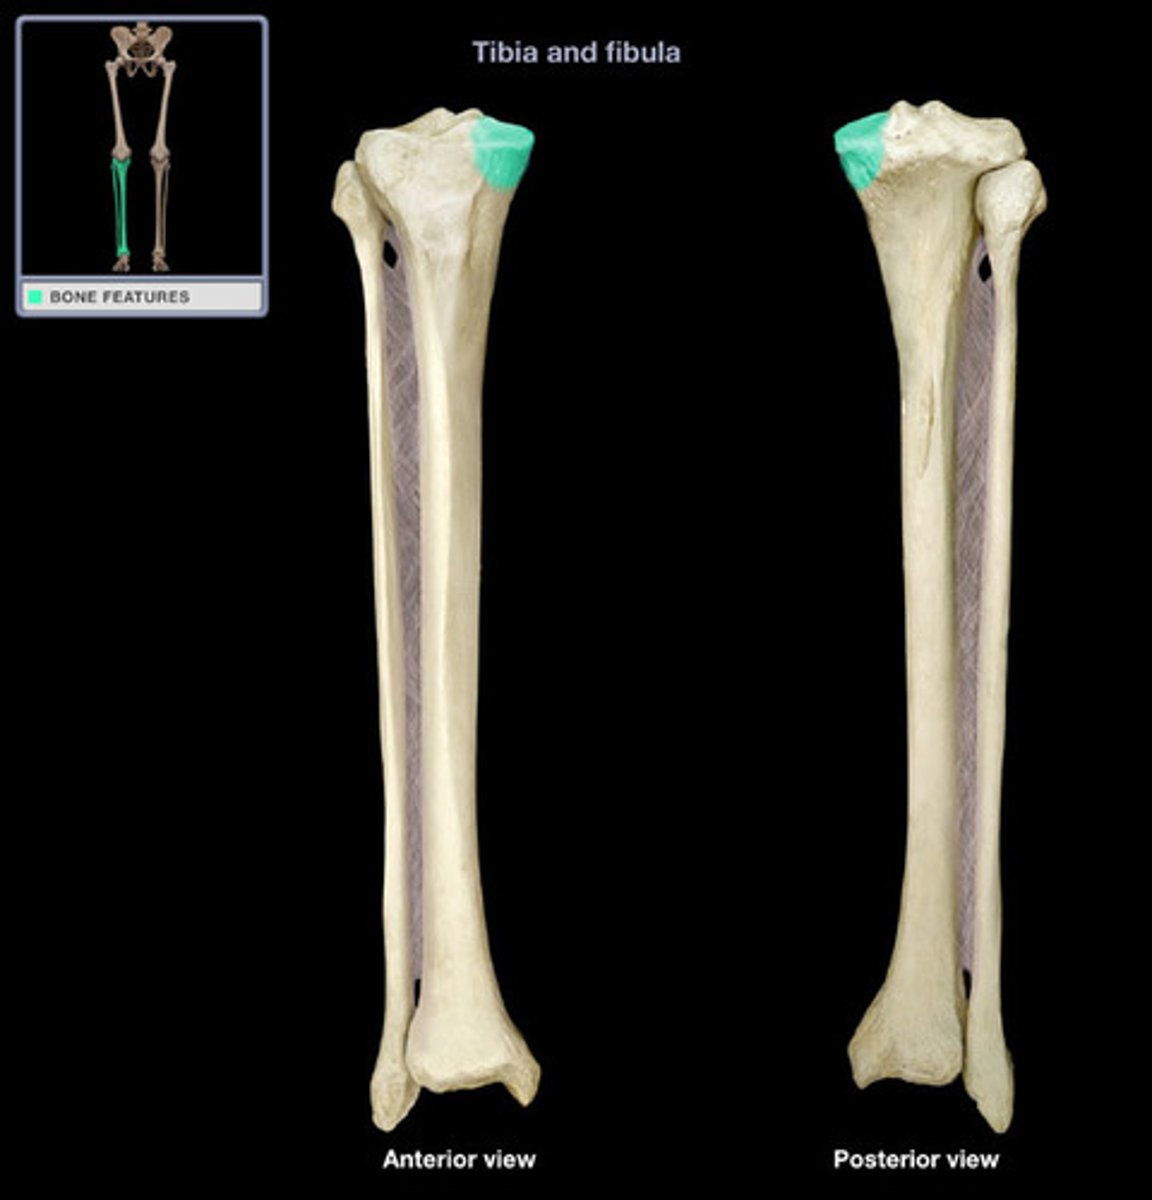

Head of tibia

#1

Medial condyle

Lateral condyle

Fibular articular facet